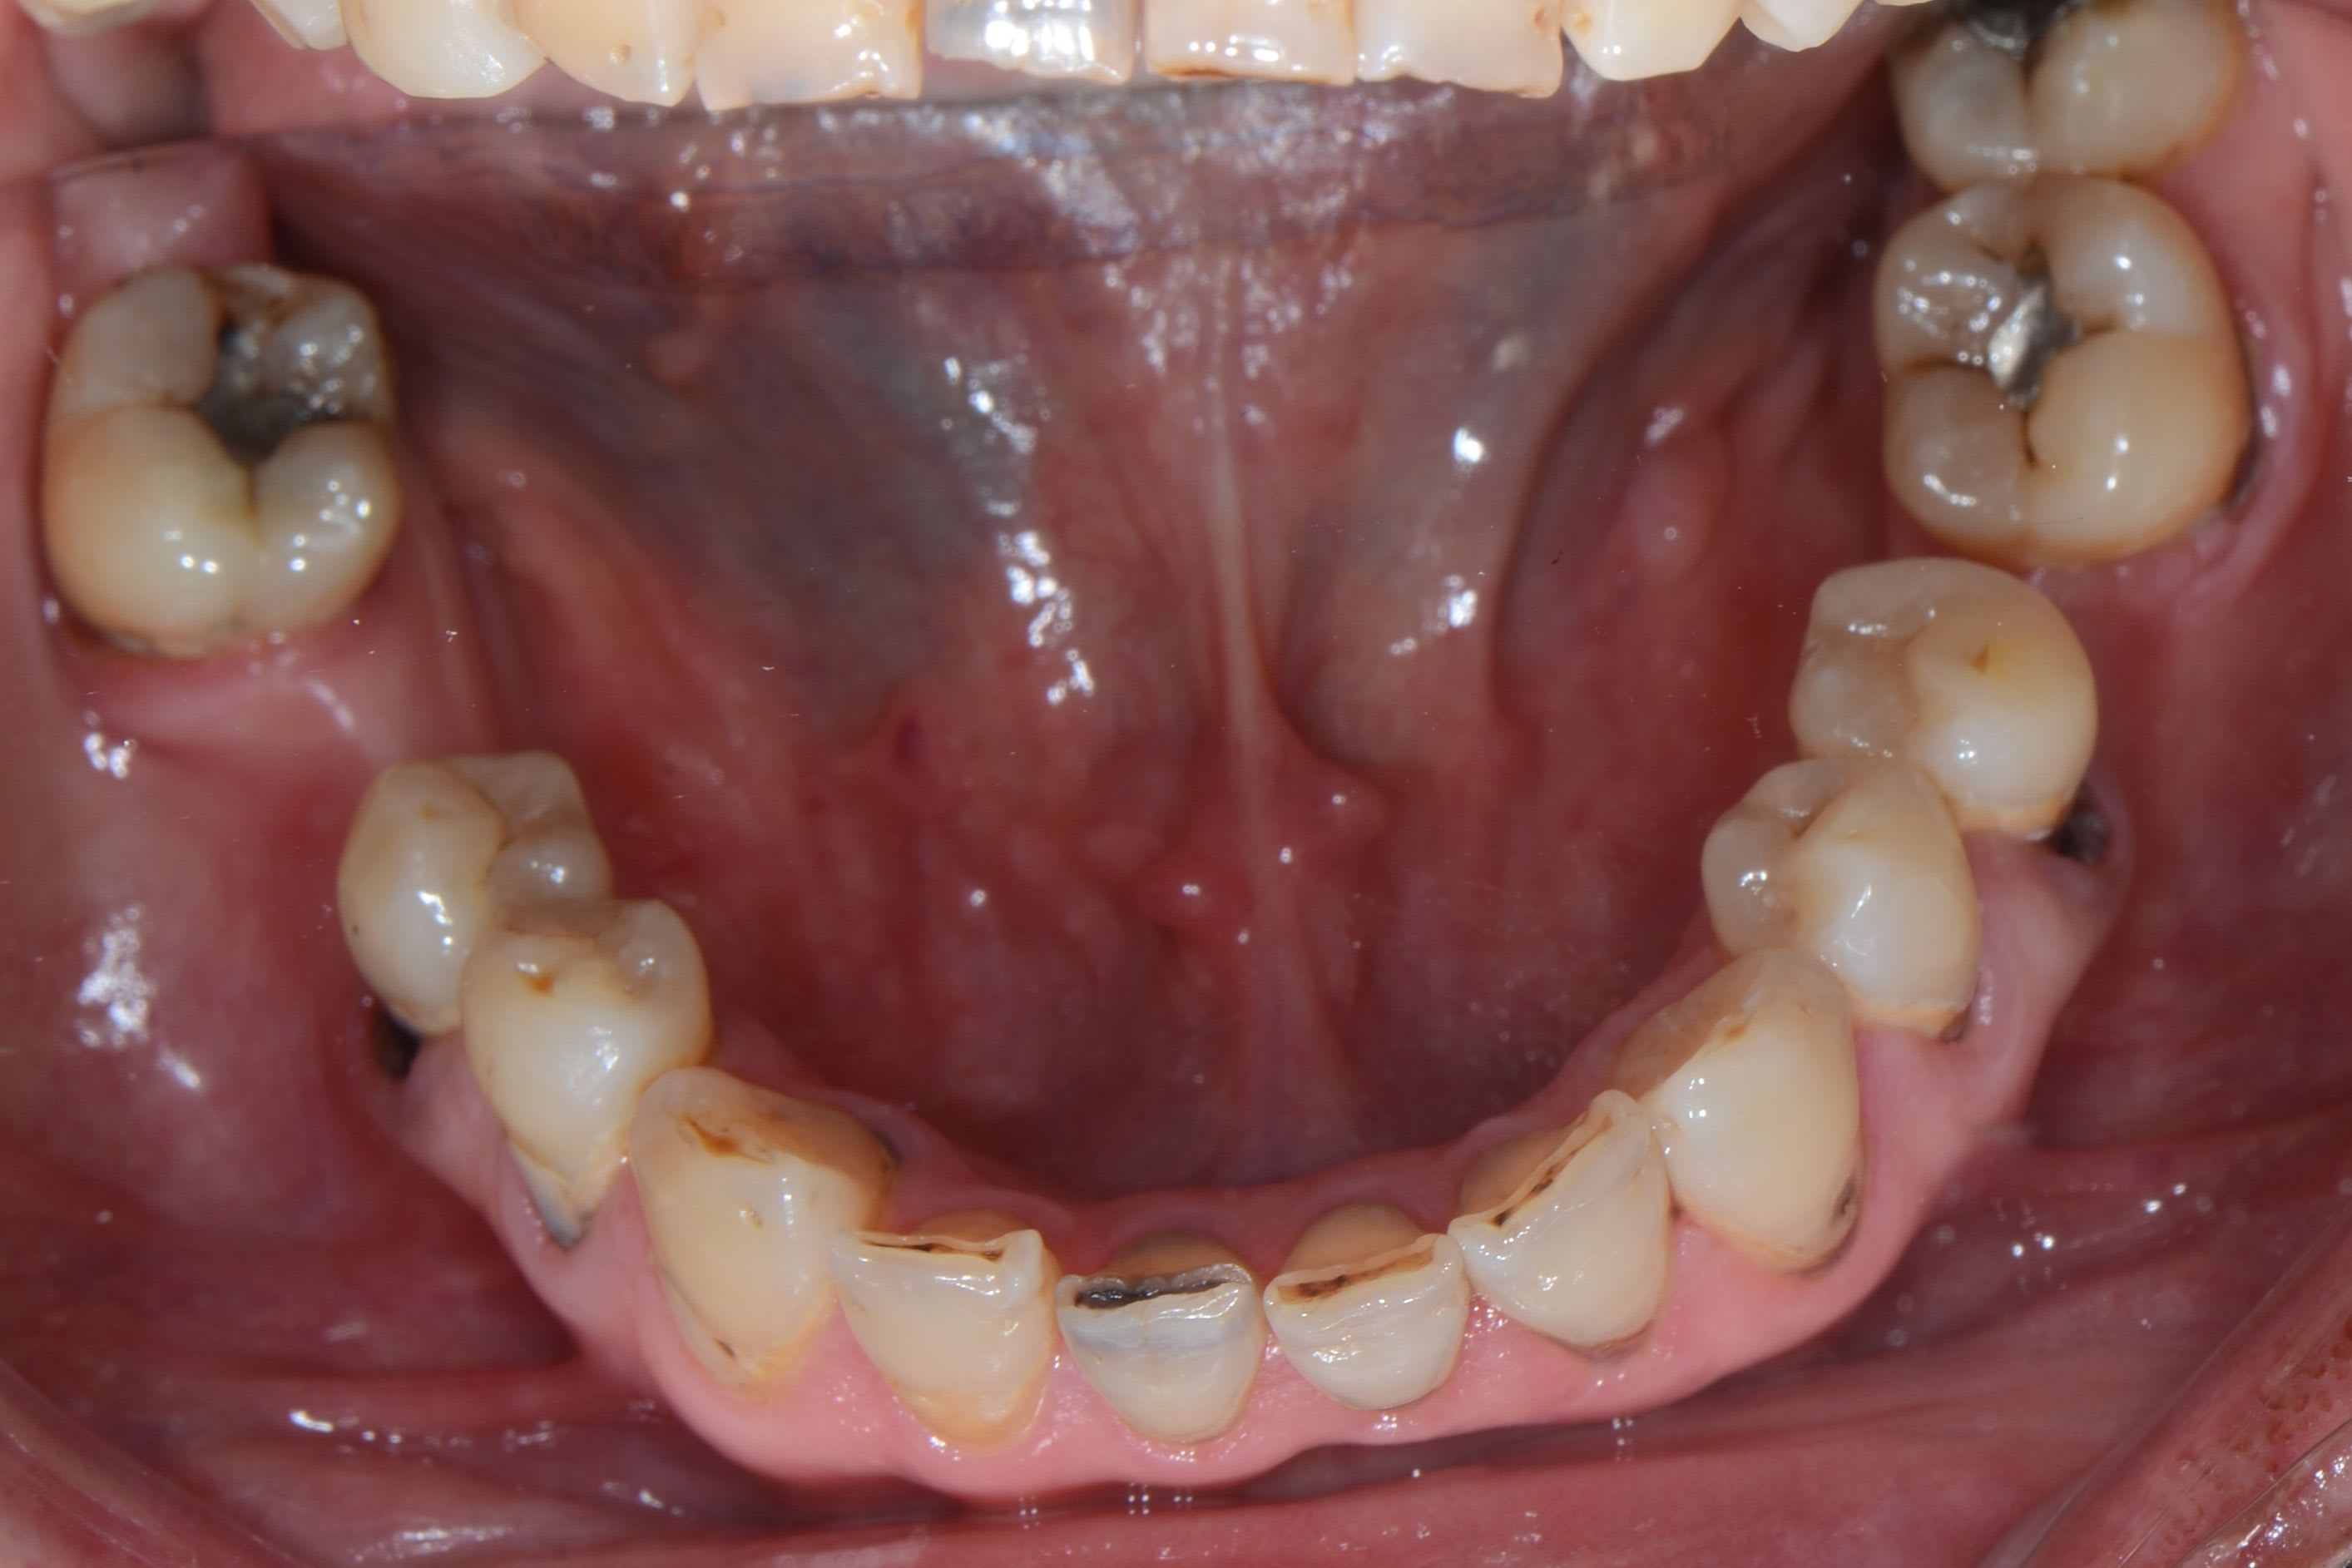

Nouvelle patiente 60 ans, pas de tabac, pas d'habitudes alimentaires prédisposantes mais syndrôme sec, très peu de salivation et ce depuis 2 ans.

A l'examen clinique, caries de collets typiques, la 45 a du être dévitalisée. Les caries sont plus importantes cliniquement que radiologiquement. Par ex les incisives mand étaient presque intégralement cariées en linguale (?).

Sur un syndrome sec le pouvoir tampon de la salive se casse la figure et la plaque est très adhérente.

Quant au matériau de restauration idéal pour une carie juxta ou sous sous gingivale... ca se complique.

le risque du CVI est que son étanchéité n'est acquise que sur une dentine parfaitement saine, or la marge cervicale d'une carie en nappe n'est pas toujours très nette, même avec un fil rétracteur. Le CVI sur des épaisseurs trop fines craquèle.